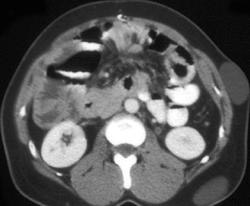

Metastatic Colon Cancer in Gardners Syndrome Patient (subcutaneous Cysts)